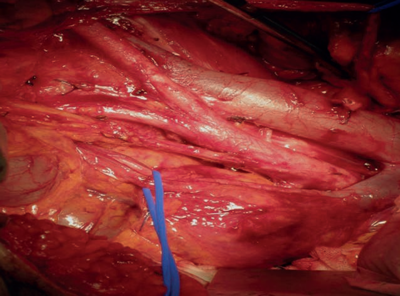

This photograph represents a retroperitoneal lymph node dissection (RPLND) for advanced germ cell tumours of the testis.

Following first-line bleomycin, etoposide, cisplatin (BEP) chemotherapy the pathology of residual tumour is found to have 6-10% viable cancer, 50% contain mature teratoma and 40% contain necrosis and fibrosis [5,6].

No further treatment is required.

A residual mass of seminoma should not be primarily resected as residual masses from seminoma tend to be intensely fibrotic and difficult to remove, although RPLND may be possible in certain centres of excellence when indicated [5]. FDG-PET scans, tumour markers and biopsies help ascertain the extent and nature of the retroperitoneal mass. Salvage therapy in the form of chemotherapy or radiotherapy are the usual options.